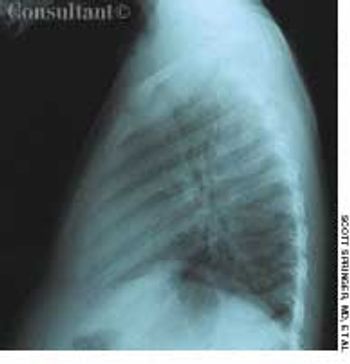

A 72-year-old woman presented for her annual physical examination. She had been treated for tuberculosis 20 years earlier. The patient did not smoke cigarettes; she denied fever, chills, and rigors.